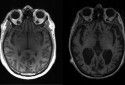

- Trous de mémoire, désorientation... Comment distinguer un simple oubli lié à l'âge d'un véritable début de maladie d'Alzheimer ? Quels signes doivent vraiment nous alerter, et comment agir pour préserver nos fonctions cognitives au quotidien ? C'est notre dossier de la semaine !